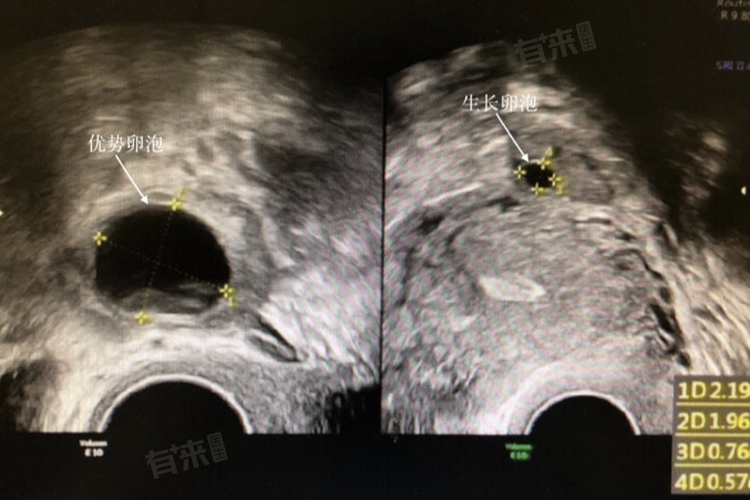

- 排卵试纸可以检测尿液中的黄体生成素水平,当LH水平达到峰值时,通常意味着排卵即将发生。通过超声波检查卵巢,可以观察卵泡的发育和排卵的迹象,从而确定排卵期。这种方法更为精确,但相对麻烦且需要医疗设备的支持。